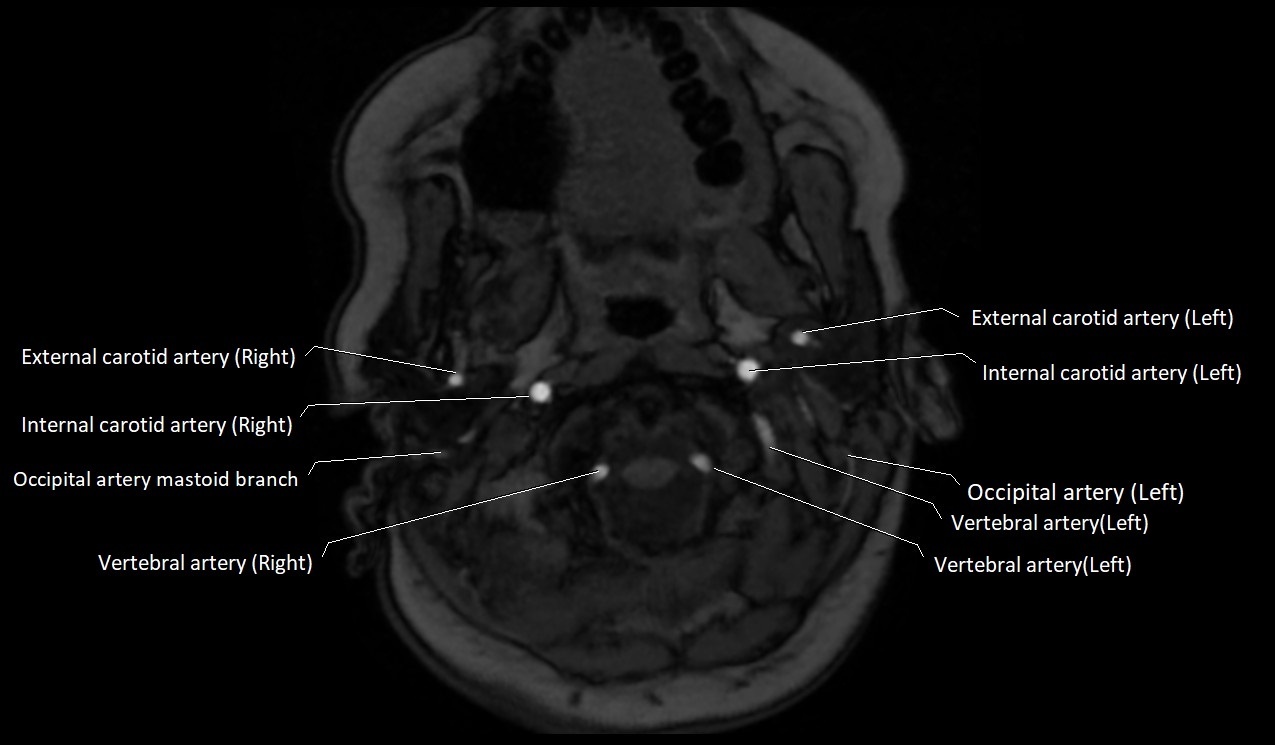

MRI images

image